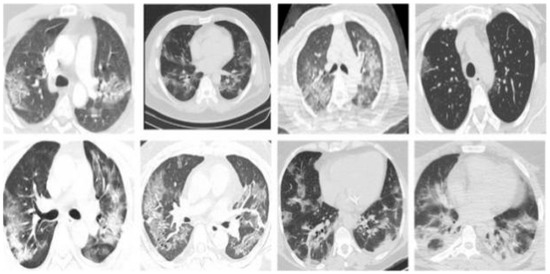

3.2. Datasets